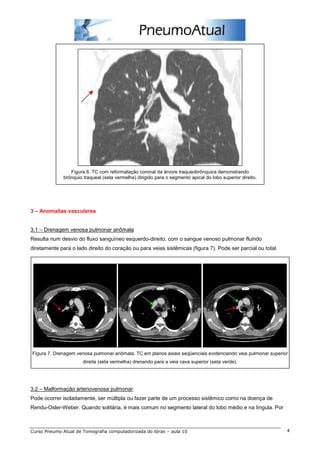

Figura 6. TC com reformatação coronal da árvore traqueobrônquica demonstrando

brônquio traqueal (seta vermelha) dirigido para o segmento apical do lobo superior direito.

2.6 – Brônquio traqueal

Ocorre quase exclusivamente à direita, até 2,0 cm cranialmente em relação à carina (figura 6).